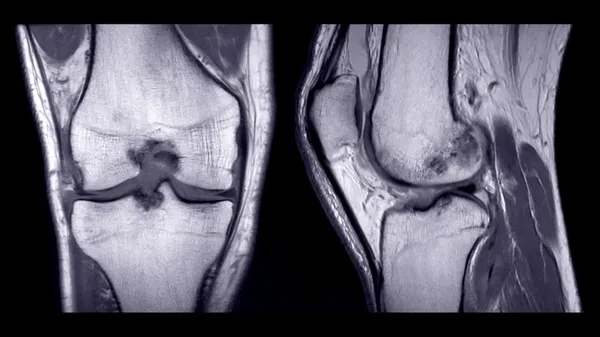

Menüsküs yırtığı, çapraz bağ yaralanması gibi eklem içi hasarlanmaları olan kişilerde kireçlenmeye gidişin daha hızlı olduğunu söyleyen Doç. Dr. Gökhan Meriç, kişinin yükünü kas dokusunun taşıdığını ve spor kas kitlesini arttırarak ekleme binen yükün azalmasına yarar sağladığını anlattı. Meriç, "Kas gücümüz ne kadar fazla ise eklemleri binen yük o kadar az olur. Bu nedenle kasları zayıf olan kişilerde eklem hasarlanması kıkırdak hasarı ve eklem içi yaralanmalar daha sık görülür." dedi.